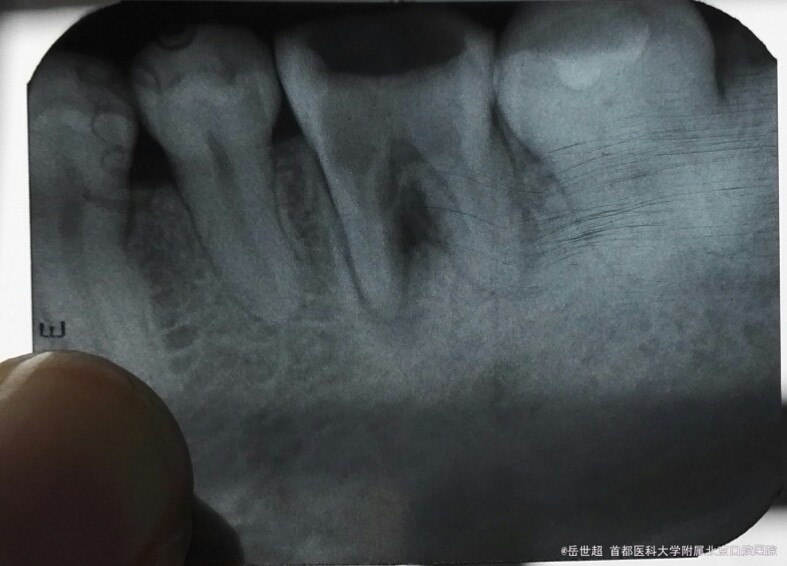

X线检查:根尖片示:左下6冠部颈部合面大面积低密度影,呈人工洞型。根管内未见充填物影响,近中见疑似底穿影像,根分歧处见大面积低密度影,面积5mm×7mm。

该例磨牙髓室底穿孔十分典型,具体症状是严重的牙髓息肉和根分叉处的炎症反应。

根尖片显示底穿面积较大 根分歧处骨破坏影像较大 不值得保留 赞同岳医生的治疗方法